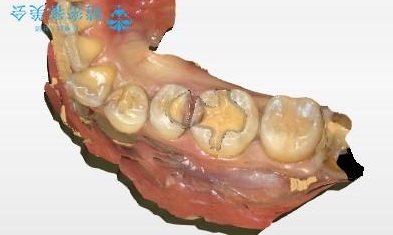

- 虫歯が複数個所あり、来院回数を抑えて治療をしたいという患者様でした。当院では光学スキャナ・ミリングマシンを設置しておりますので、1日でセラミック修復治療を完了させました。術後も良好な経過をたどっています。

メタル修復物の場合X線を通さない性質があり、レントゲン写真を撮るとメタルの部分が真っ白に写ってしまうため、詰め物の下の虫歯が分かりにくくなってしまうというデメリットがあります。これに対し、今回の即日セラミック修復に使用したMarkⅡという材料は、レントゲン写真からもわかる通り歯の一番外側の部分(エナメル質)と同程度のX線透過性を持ちます。そのため装着後も定期的なメンテナンスにより虫歯の再発を早期に発見できるメリットがあります。